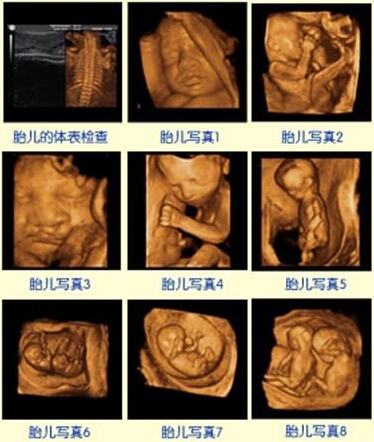

福州台江医院作引进的美国GE四维彩超对胎儿无辐射作用,能直观、立体显示人体器官,对胎儿畸形,如唇裂、腭裂、骨骼发育异常、心血管畸形等疾病。作为福建省第2家引进美国GE四维彩超的专业产科医院,我院的每一台四维彩超都是由医师亲自操作,家属可陪同观看,全程大约需要花费30-40分钟!

这段时间检查,胎儿较小,羊水适中,胎儿活动度大,体表也比较丰满,有利于胎儿四维超声成像和胎儿畸形筛查,是排畸的时期。

美国GE四维彩超能够多方位、多角度地观察宫内胎儿的生长发育情况,为早期诊断胎儿先天性体表畸形和先天性心脏疾病提供更精准的科学依据。